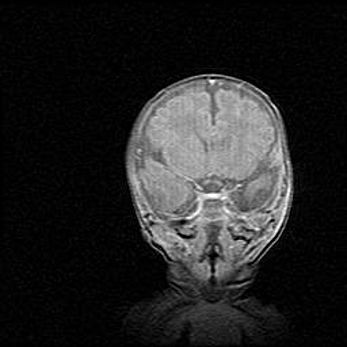

Наружная гидроцефалия с возможной атрофией височных областей.

Возраст: 28 дней

Вес: 3670 г

Пол: мужской

Окружность головы: 38 см

Срок гестации: 40 недель

Гидроцефалия головного мозга у новорожденных – это заболевание, которое характеризуется скоплением избыточного количества спинномозговой жидкости в желудочковой системе головного мозга в результате затруднения её перемещения от места выработки к месту поглощения в кровеносную систему или вследствие нарушения абсорбции. При открытой наружной форме гидроцефалии у новорожденных расширяются и переполняются субарахноидные пространства.

При нормотензивных  формах,  которые,  как  правило,  являются  следствием  перенесенных ишемических  повреждений  паренхимы  мозга,  возможно  сочетание микроцефалии  с нормотензивной гидроцефалией. В основе данных изменений лежит атрофия больших полушарий с преимущественной  локализацией  в  лобно-височных  областях.